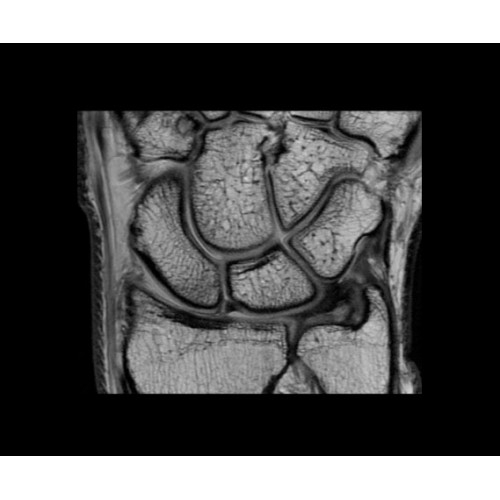

SIGNA PET/MR 3.0T — это гибридная система, в которой совмещаются две принципиально разные технологии — магнитно-резонансную томографию (МРТ) и позитронно-эмиссионную томографию (ПЭТ). Система отличающийся высокой чувствительностью и эффективностью и предназначена для диагностики в области онкологии, неврологии, кардио-васкулярных исследований, исследований воспалительных процессов.

Кроме того, в результате использования технологии TOF и инновационной технологии реконструкции Q.Clear вы сможете добиться прекрасного соотношения сигнал/шум. А благодаря технологии нулевого времени эхо (ZTE) визуализировать костную структуру без ионизирующего излучения. Все эти разработки для улучшения качества сканирования и точности анализа помогут вам использовать весь потенциал ПЭТ/МРТ.

• МРТ с функцией нулевого времени эхо (ZTE) отличается точностью, возможностью персональных настроек и отсутствием ионизирующего излучения. Она приходит на смену традиционному исследованию на основе рентгеновского излучения. МРТ с функцией нулевого времени эхо (ZTE) на базе SIGNA ПЭТ/МРТ является более надежной и быстрой по сравнению с системами, использующими сверхмалое время эхо (UTE).